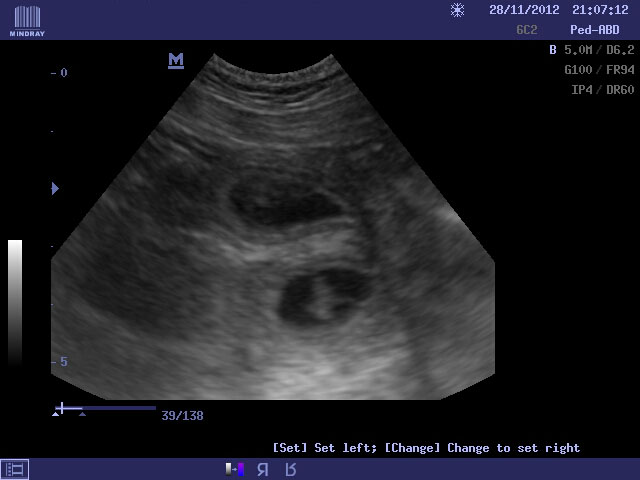

Zdravíme všechny naše kamarády, známé a vůbec všechny návštěvníky našich stránek. Po nedávné aktualitě o krytí naší Růženky v Itálii přicházíme s další, neméně významnou skvělou zprávou. Musím se přiznat, že jsme to sice předvídali, ale přesto jsme byli rádi, když jsme měli informaci potvrzenou od znalce :o) našeho milého pana veterináře.